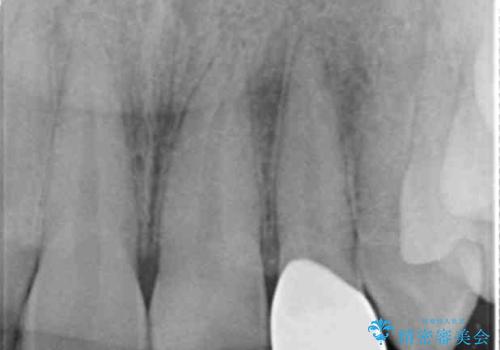

噛み合わせが深く、前歯の突き上げが大きいため欠けの繰り返しを防ぐべくセラミッククラウンによる補綴を行うこととしました。

- 「欠けてしまった前歯のコンポジットレジン修復をくり返していたが、すぐ外れてしまい困っている。」

、と前歯の欠けの改善を求めて来院されました。